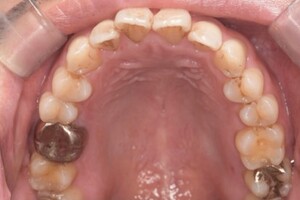

Before

After

基本情報

| 年齢・性別 | 30代・女性 |

| 主訴 | 定期検診 |

| 治療内容 | PMTC |

| 治療期間 | 60分 |

| 治療費 | 5,750円 |

| リスク・副作用 | しみる可能性があります。 |

| 治療方針 | PMTCでステインの除去。 |

| 担当者所見 | ステインが付きやすいため、3カ月毎の定期検診で除去する。 |